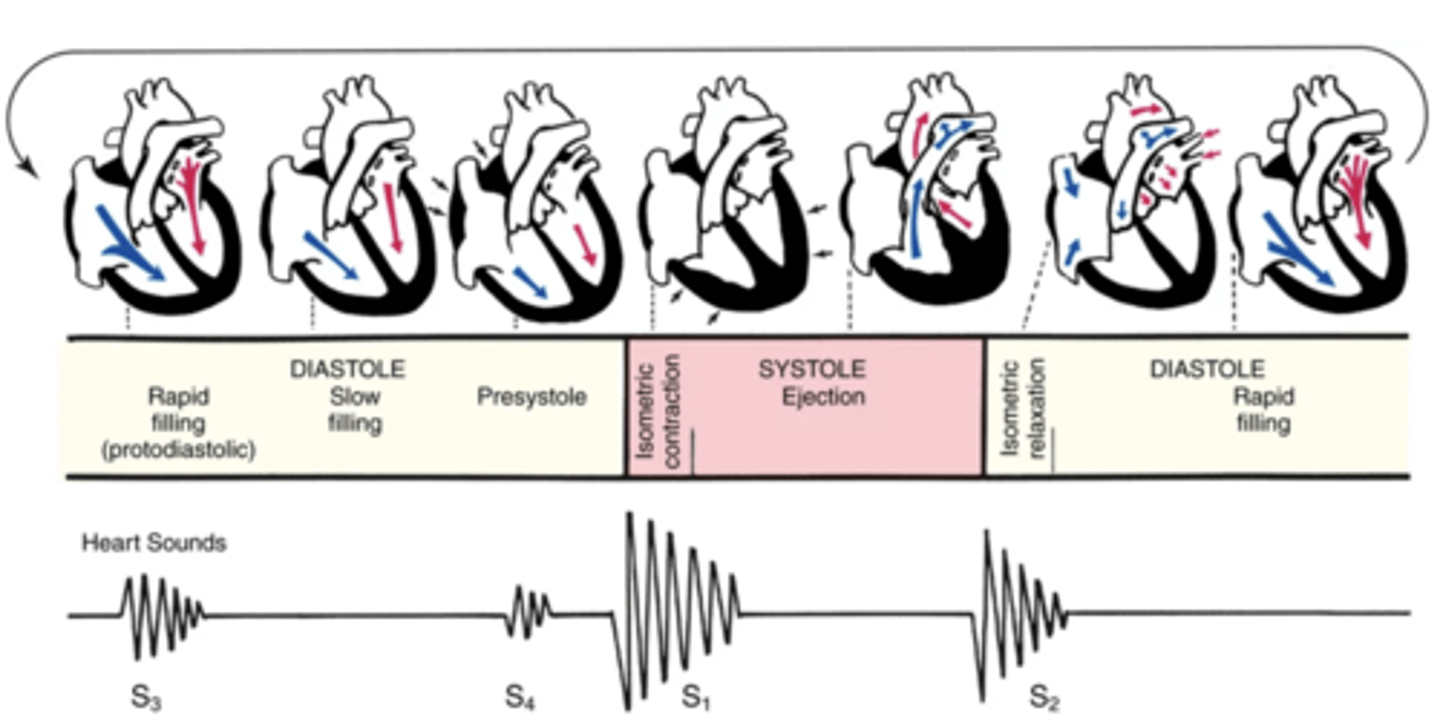

Cardiac Cycle

A complete heartbeat consisting of contraction and relaxation of both atria and both ventricles

2 Phases of the Cardiac Cycle

- Diastole

- Systole

Diastole

The phase of the cardiac cycle where the ventricles relax and fill with blood (relaxation)

Systole

The phase of the cardiac cycle where blood is pumped from the ventricles and fills the pulmonary and systemic arteries (contraction)

Steps of Diastole

1.) Ventricles relax

2.) AV valves open

3.) Higher atrial pressure causes passive ventricular filling (early/protodiastolic filling)

4.) The atria contracts and pushes the last amount of blood into the ventricles (atrial systole)

Steps of Systole

1.) High ventricular pressure causes AV valves to close

2.) Ventricles contract, increasing ventricular pressure

3.) SV valves suddenly open, resulting in a quick ejection of blood

4.) SV valves close once ventricular pressure falls below aortic pressure

The 4 Heart Sounds

- S1

- S2

- S3

- S4

S1

The first heart sound that occurs with the closure of the AV valves, beginning systole

S2

The second heart sound that occurs with the closure of the SV valves, ending systole

S3

The third heart sound that sometimes occur when the ventricles are resistant to filling during protodiastole

S4

The fourth heart sound that sometimes occur when the ventricles are resistant to filling during the end of diastole (presystole/atrial systole)